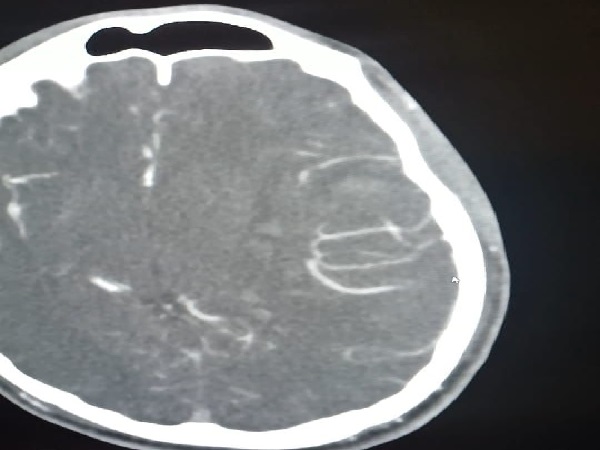

تمكن بفضل من الله فريق طبي من قسم جراحة المخ والاعصاب بمستشفى الملك خالد التابع للتجمع الصحي بتبوك من انقاذ حياة شاب بالعشرين من عمره وصل الى قسم الطوارئ وهو في حالة فقدان للوعي وبعد عمل الفحوصات اللازمة وتصوير الاوعية الدموية الدماغية تبين وجود نزيف دماغي حاد في الجهة اليسرى كذلك وجود تشوه خلقي دموي وعائي كبيرا جدا.

وأوضح الفريق الطبي من قسم جراحة المخ والاعصاب بالتجمع بانه تم فورا ادخال المريض الى غرفة العمليات واجراء استئصال للأوعية الدموية مجهريا حيث استغرق اجراء العملية أكثر من 5 ساعات تكللت ولله الحمد بالنجاح كما تم تحويل المريض لقسم التنويم بمتابعة وإشراف الفريق الطبي.

واكد الفريق الطبي بان حالة المريض تحسنت تدريجيا ولم تكن هناك أي مضاعفات اثناء وبعد العملية وبدا بحركة الأطراف إضافة الى فتح العينين ولله الحمد.